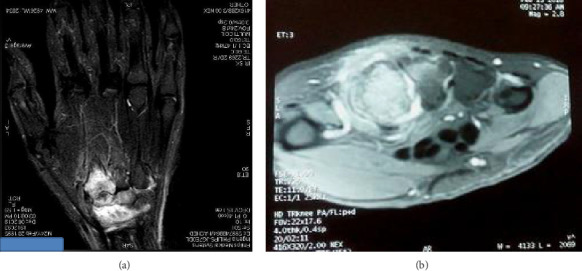

Osteoid osteomas predominantly occur in the cortices of long bones, with the femur and tibia being the most commonly affected sites. However, they can occasionally present in atypical locations, such as the carpus, which can lead to diagnostic confusion with other conditions. This case report details an intraarticular osteoid osteoma in the trapezoid bone. Initial evaluations, including standard radiographs, joint ultrasound, and wrist MRI performed twice, initially pointed toward a diagnosis of wrist synovitis. This case underscores the diagnostic challenges posed by atypical presentations of osteoid osteomas. Given the edema present in the carpal bones alongside the synovitis, we performed a hand CT scan, which raised doubts about the appearance of the nidus and histopathological examination confirmed the diagnosis. Clinical symptoms, including pain and functional limitations, were completely resolved following surgical excision.